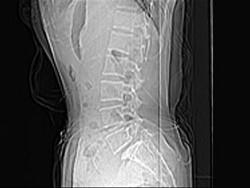

问题 男,29岁,腰痛伴下肢轻度麻木,有外伤史,请结合所提供图像,选择最佳答案 ( )

选项 A、S向后滑脱 B、未见异常 C、L向后滑脱 D、S向前滑脱 E、L向前滑脱

答案 E